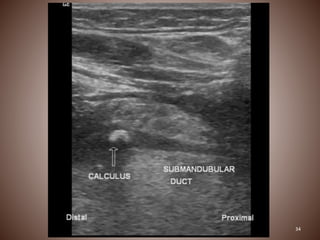

Submental region which shows a small hyperechoic structure, a sialolith.

31 Submental region whichshows a small hyperechoic structure, a sialolith.

32 Parotid gland showinga small sialolith .